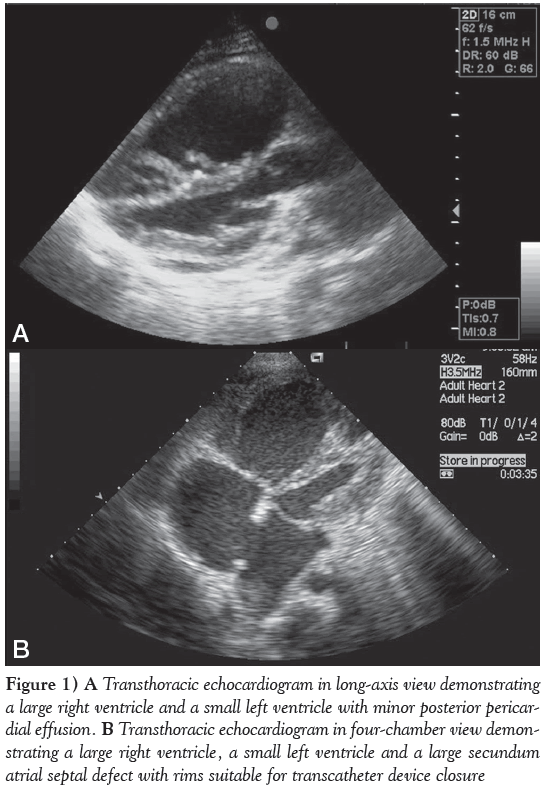

On echocardiography, her heart morphology revealed a very small left ventricle (LV) – left ventricular end diastolic diameter of only 26 mm (Figure 1A) – with mild to moderate nonrheumatic mitral valve regurgitation, a very large right ventricle (RV) and a 22 mm secundum ASD (Figure 1B), with reasonable rims morphologically amenable to percutaneous device occlusion. The shunt was mainly left to right; however, a small, narrow, systolic jet of tricuspid valve incompetence crossed the ASD from right to left. The tricuspid valve regurgitation jet velocity was 5 m/s, suggestive of systolic pulmonary artery pressure (PAp) of approximately 120 mmHg, while the systemic pressure was 95/65 mmHg. A very small pericardial effusion was also noted.

Figure 1: A Transthoracic echocardiogram in long-axis view demonstrating a large right ventricle and a small left ventricle with minor posterior pericardial effusion. B Transthoracic echocardiogram in four-chamber view demonstrating a large right ventricle, a small left ventricle and a large secundum atrial septal defect with rims suitable for transcatheter device closure